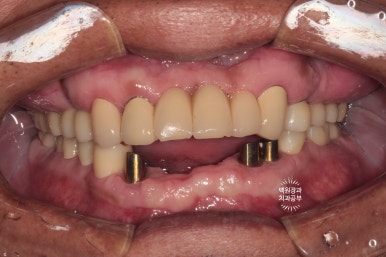

시간이 흘러 잇몸이 아물고 위 임플란트의 임시 보철물을 제작해 드렸습니다.

왼쪽은 임플란트에 맞춤형 지대주 (custom abutment)를 연결한 사진이고,

오른쪽은 그 맞춤형 지대주에 임시치아 (temporary crown)을 접착한 사진입니다.

색상이 다소 맞지 않습니다만, 이는 플라스틱 재질과 비슷한 임시치아이므로 기능을 잘 하실 수 있는지 평가하는데 집중해봅니다.!!

양쪽 어금니가 잘 물리고 이제 밥을 먹을 수 있어요.

shade guide를 사용하여 치아의 색상을 측정해 봅니다.

기존에 사용하고 계시던 위 앞니의 보철물이 B3 색상에 가까웠기 때문에, 그 색상으로 제작하기로 결정!!

치아의 색상을 결정할 때는 환자 안모의 피부톤도 감안하여서 정해야 합니다.

어두운 색상의 피부를 가진 60대 환자분에게 어울리는 치아 색상으로 정해보았어요. 너무 하야면 가짜같아요...